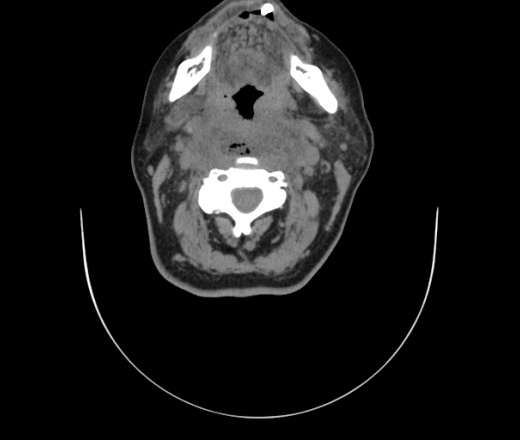

Женщина поступила в х/о спустя 4 дня после того как при употреблении карася подавилась костью.

Наличие газа в средостении на протяжении тел С2-С6 (медиастинальна эмфизема); рыбная кость на уровне тела С6.

При всем уважении, но говорить о медиастинальной эмфиземе, оценивая мягкие ткани шеи, как-то слишком резко. На мой взгляд, это ретрофарингеальное пространство.

Согласен с Вами; конечно, наличие газа в клетчатке ретрофарингеального пространства (затмение с опечаткой..). К сожалению, процесс "продвигается" к медиастиниту. Но почему никто, не отмечает наличие рыб. кости; или это для Всех очевидно?

Так вы уже отметили. Хотя ориентировал бы не скелетотопически, а на перстнечерпаловидный сустав.

Кость то мы сразу выявили, размеры где то 17*2мм, но ее так и не получается найти в этой каше